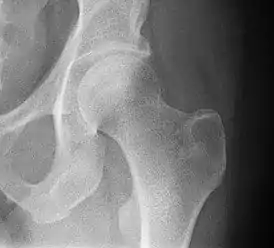

![]() Рентгенограмма, демонстрирующая перелом шейки бедра | |

4) Данных рентгенологического обследования — выполняется рентгенография тазобедренного сустава в прямой проекции. Наличие линии перелома на рентгенограмме служит окончательным, объективным подтверждением предварительно выставленного диагноза. Иногда для постановки диагноза может потребоваться магнитно-резонансная томография или компьютерная томография.